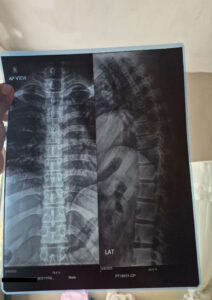

Varun, 31 ans, souffre d’une hernie discale cervicale dégénérative C4-5 avec radiculopathie. Financièrement, son traitement, son billet d’avion, son hébergement et son allocation de subsistance coûteront Rs 1,148,256 .